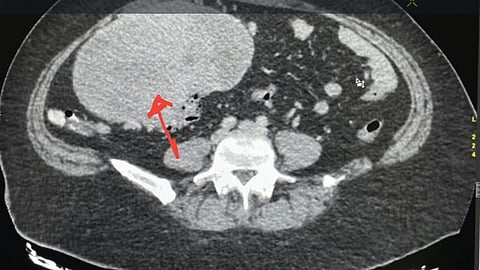

وكان اكتشاف الورم بمحض الصدفة عبر أطباء الأشعة في المجمع، وبعد التشخيص الدقيق من قبل أطباء الأنسجة وتقييم الحالة بعناية، تقرر إجراء العملية الجراحية.

ويُعد الورم الذي تم استئصاله من الأورام العصبية في جدار الأمعاء ويُصنف ضمن الحالات النادرة عالميًا.